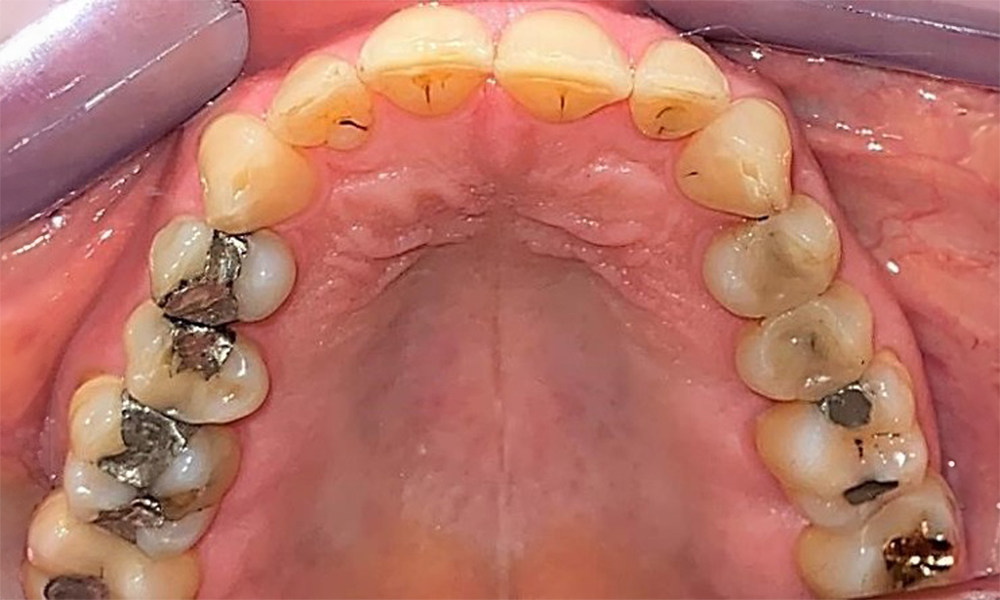

Okklusalansicht Oberkiefer. Insuffiziente Amalgamfüllung 14 mit Randspalt. © Dr. R. Krapf

Abb. 5 Okklusalansicht Oberkiefer. Insuffiziente Amalgamfüllung 14 mit Randspalt. © Dr. R. Krapf

Der Patient hat ein vollbezahntes Gebiss mit 28 Zähnen, an welchen sich im Molaren- und Prämolarenbereich Amalgamfüllungen und Compositefüllungen befinden. An Zahn 14 zeigt sich ein sichtbarer klinischer Randspalt. Zahn 27 hat ein suffizientes Goldinlay. Zudem zeigen sich generalisierte Attritionen und Abrasionen. (Abb. 2, Abb. 3, Abb. 4, Abb. 5, Abb. 6)